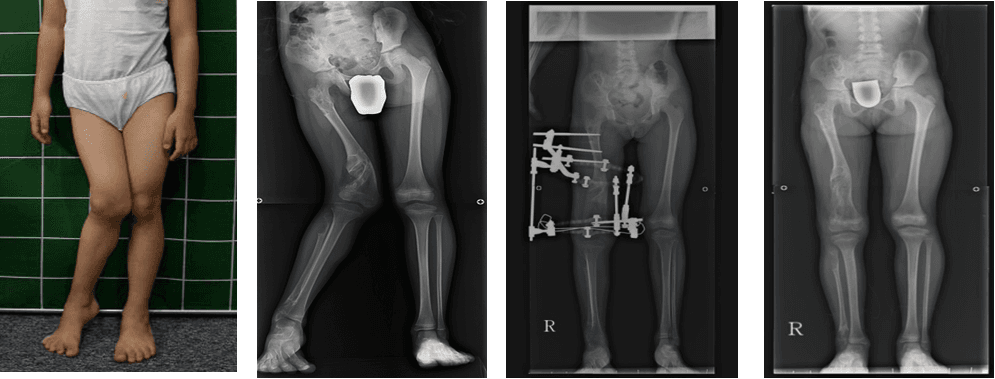

왼쪽다리에 변형이 온 소아마비 환자의 하지 교정술

소아마비환자의 하지변형에 대한 교정